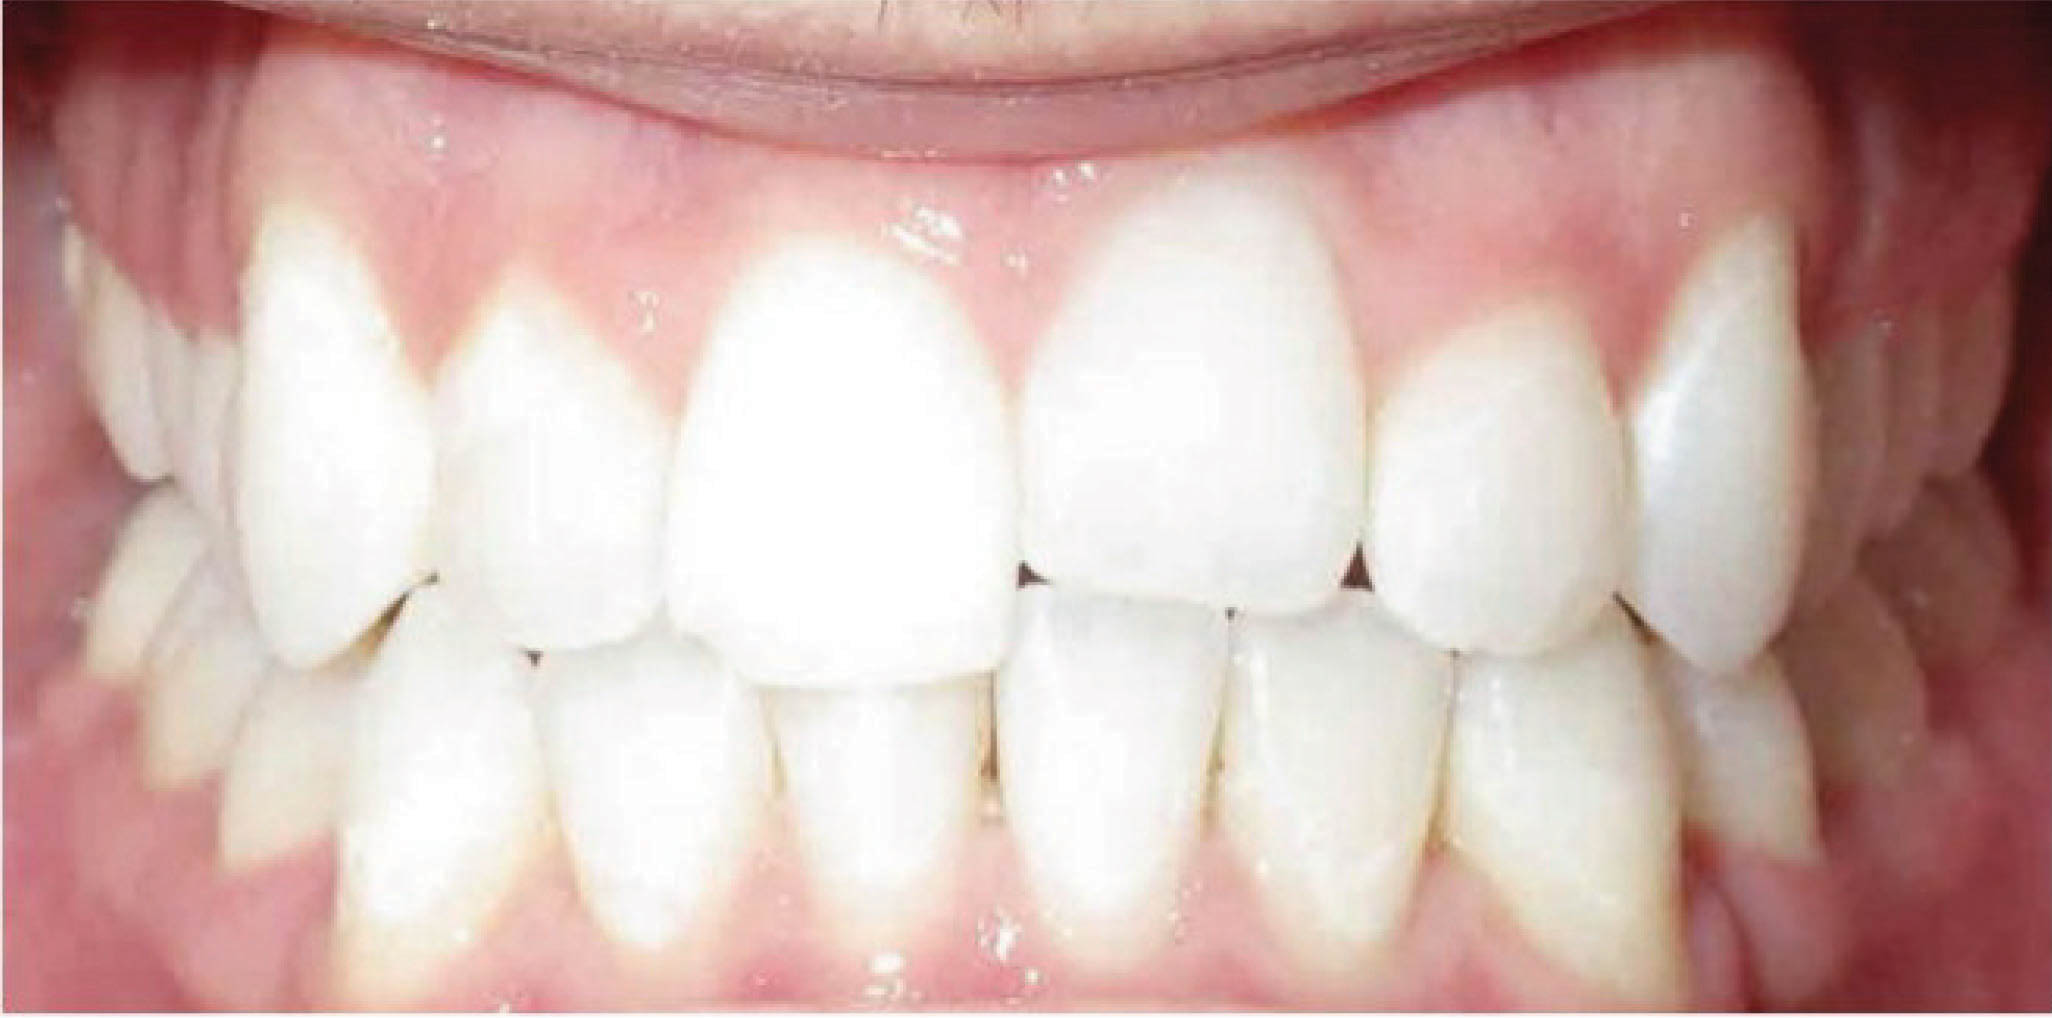

با این دستور، لابراتوار درمان اضافه روی مدل کامپیوتری انجام میدهد و اوربایت نهایی را صفر در نظر میگیرد. برای چندمین بار تکرار میکنیم که آنچه بعنوان طرح کامپیوتری میبینید، وضعیت نهایی دندانها نخواهد بود بلکه نوع اعمال نیرو برای رسیدن به یک وضعیت مطلوب است. این وضعیت مشابه همان سیم کِرودار است که وضعیت چیدمان دندانها در پایان کار نمیباشد بلکه نوع اعمال نیرو برای رسیدن به یک وضعیت مطلوب است. همانطور که در بیمار 158-6 مشاهده میکنید، در انتهای درمان کِرواسپی معکوس مشاهده نمیشود، بلکه کِرواسپی صاف و اوربایت طبیعی گشته است. در طراحی این بیمار اوربایت را صفر در نظر گرفتیم تا به اوربایت طبیعی دست پیدا کنیم.

شکل 158-6

بیمار بعدی هم همین گونه است (شکل 159-6) و 2mm اینتروژن بیشتر برای انسیزورهای بالا و پایین در نظر گرفته شده تا اوربایت صفر بشود (شکل 160-6). در پایان درمان (شکل 161-6) کرو اسپی صاف و اوربایت طبیعی گشته است و به نتایج زیبایی و فانکشنال خوبی دست پیدا نمودهایم.